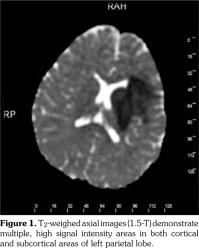

Based on these clinical findings, the patient was diagnosed as HSP, and the skin biopsy showed leukocytoclastic vasculitis with histopathologic evidence of immunoglobulin (Ig) A and M deposition based on direct immunofluorescence staining. A written informed consent was obtained from the parent of patient. The patient was being followed-up as an out-patient. On the 15th day of his follow-up, he admitted to the emergency department by sudden focal tonic- clonic convulsions and unconsciousness. He was not able to use his right hand and foot, also he could not talk. His blood pressure was 105/70 mmHg. Fundoscopic examination was unremarkable. The physical examination showed aphasia, right sided central facial paralysis, and hemiplegia on the right. Deep tendon reflexes were exaggerated and there was extensor plantar response on the right side. Cerebellar functions and sensory testing were normal. In acute laboratory evaluation, serum electrolytes and glucose levels were normal. Immediate 1.5 Tesla magnetic resonance imaging (Magnetom Avanto, Siemens Medical Solutions, Erlangen, Germany) demonstrated multiple, high signal intensity areas on T2-weighted images in both cortical and subcortical areas of the left parietal lobe (Figure 1). Magnetic resonance angiography revealed narrowing and irregularities in the lumen of left middle cerebral artery resembling vasculitis (Figure 2). Electroencephalography showed diffuse generalized delta slow waves of moderate amplitude without epileptiform discharges. Renal angiography and mesenteric vasculature were normal. The patient was diagnosed as cerebral vasculitis due to HSP. Intravenous pulse methylprednisolone (30 mg/kg/day) was given for three consecutive days; subsequently the patient received oral steroids (2 mg/kg/day) for cerebral vasculitis. Because of the unchanged clinical status of the patient, pulse cyclophosphamide therapy was begun. Patient received 500 mg/m(2)/day pulse cyclophosphamide monthly for three months. He showed clinical improvement after cyclophosphamide therapy. The follow-up magnetic resonance angiography, performed 15 days after the initial one, demonstrated substantial improvement of cerebral lesions (Figure 3). His steroid treatment was stopped by tapering within six months. He had speech therapy and also physical rehabilitation and therapy for two years. He has been followed-up without any sequel for four years.

In conclusion, cerebral vasculitis should be suspected in all cases of HSP with neurologic manifestations. Magnetic resonance angiography is the modality of choice for diagnosis and follow-up evaluation. Although treatment options are numerous and controversial, combined therapy with pulse corticosteroid and pulse cyclophosphamide should be the first choice in pediatric patients.